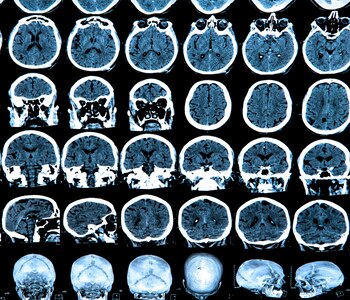

En el Laboratorio de Parkinson Experimental del Instituto de Investigaciones Farmacológicas (ININFA, CONICET-UBA), un grupo de investigadores liderados por Juan Ferrario, investigador adjunto del CONICET, estudia mecanismos moleculares para entender por qué la terapia contra el Parkinson produce disquinesias: un efecto secundario de la L-DOPA o levodopa, la droga que se usa para combatir los daños que produce esta enfermedad neurodegenerativa.

"El puntapié inicial para las investigaciones – recuerda Gershanik – fue una resistencia al uso de la L-DOPA en la década del '90. En aquel momento se difundía la idea de que este medicamento era tóxico. Entonces nosotros empezamos a hacer una serie de experimentos para evaluar los efectos del tratamiento con levodopa en el cerebro de ratas parkinsonianas y demostramos la ausencia de toxicidad. A partir de ahí, profundizamos y es donde interviene Juan, tratando de identificar cambios a nivel molecular determinados por la levodopa, en una serie de experimentos innovadores que nos permitieron encontrar varias piezas del rompecabezas molecular".